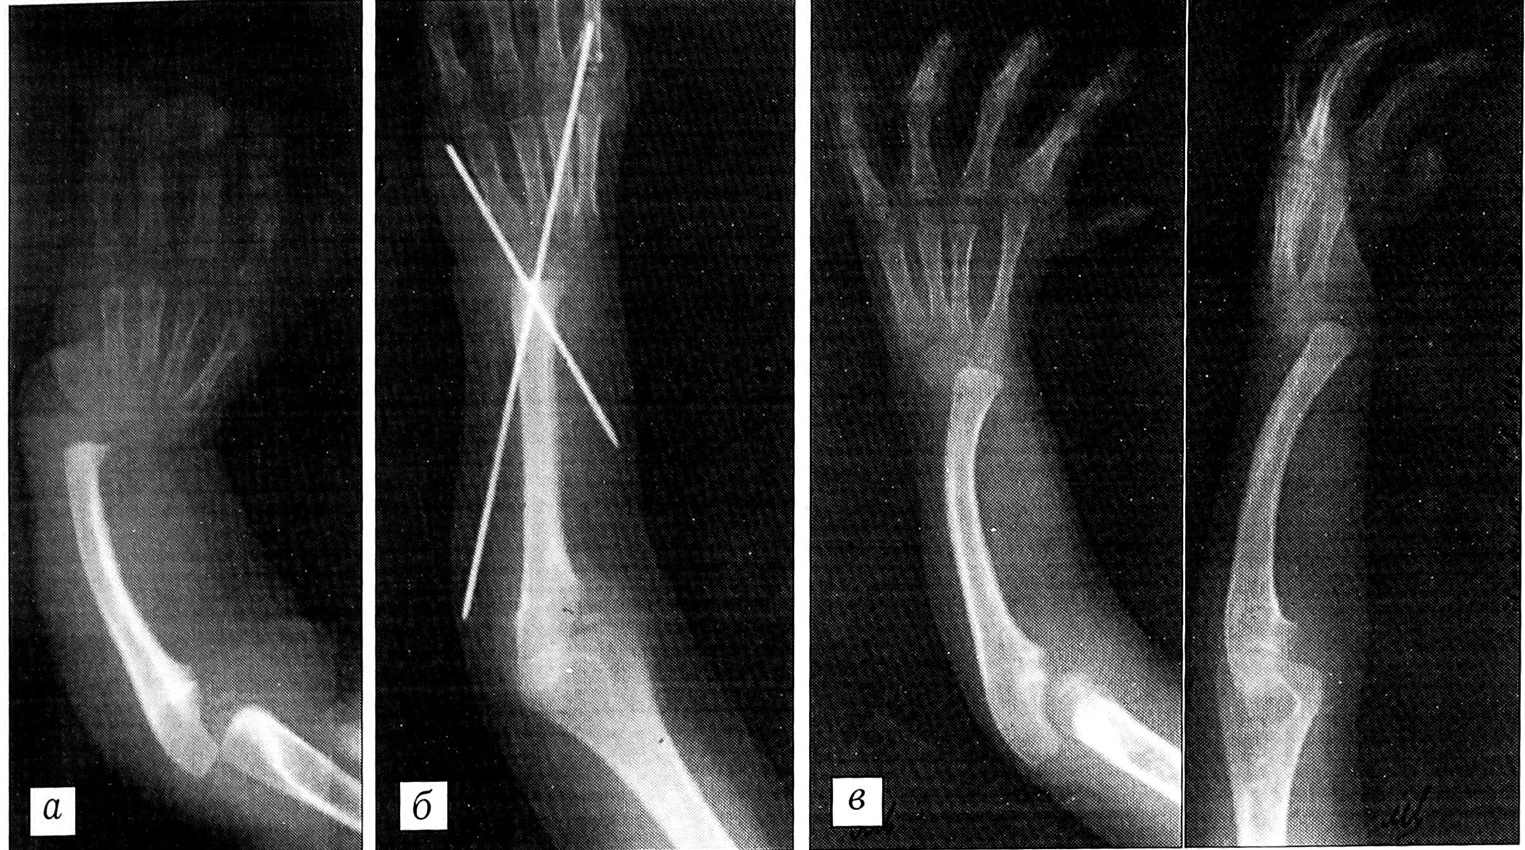

Рис. 1. Рентгенограммы левой верхней конечности больной 3. с врожденной лучевой косорукостью.a — до операции (в возрасте 1 года);б — после операции одноэтапной центрации кисти с фиксацией спицами Киршнера (в возрасте 5 лет);б — через 2 года после операции: имеется вывих кисти к тылу, что потребовало повторного оперативного вмешательства.

Рис. 2. Рентгенограммы правой верхней конечности больного М. с врожденной лучевой косорукостью.а — до операции (в возрасте 4 лет);б — после операции центрации кисти с применением двухэтапной методики (в возрасте 6 лет);в — через 7 лет после операции: из-за не устраненной ранее разгибательной контрактуры локтевого сустава произошел рецидив деформации, несмотря на достигнутое смещение кисти на дистальный конец локтевой кости.